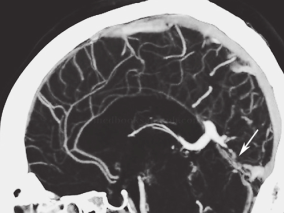

1小时条评论一、病历摘要:患者女性,20岁,主因头痛、呕吐9天,意识障碍5天于2006年7月30日以静脉窦血栓形成收入神经内科重症监护病房(N‐ICU)。患者入院前9天外出游玩回家后感头痛,随后呕吐10余次,进食后明显,不伴发热、精神异常、肢体活动障碍等。按中暑口服药物未见明...